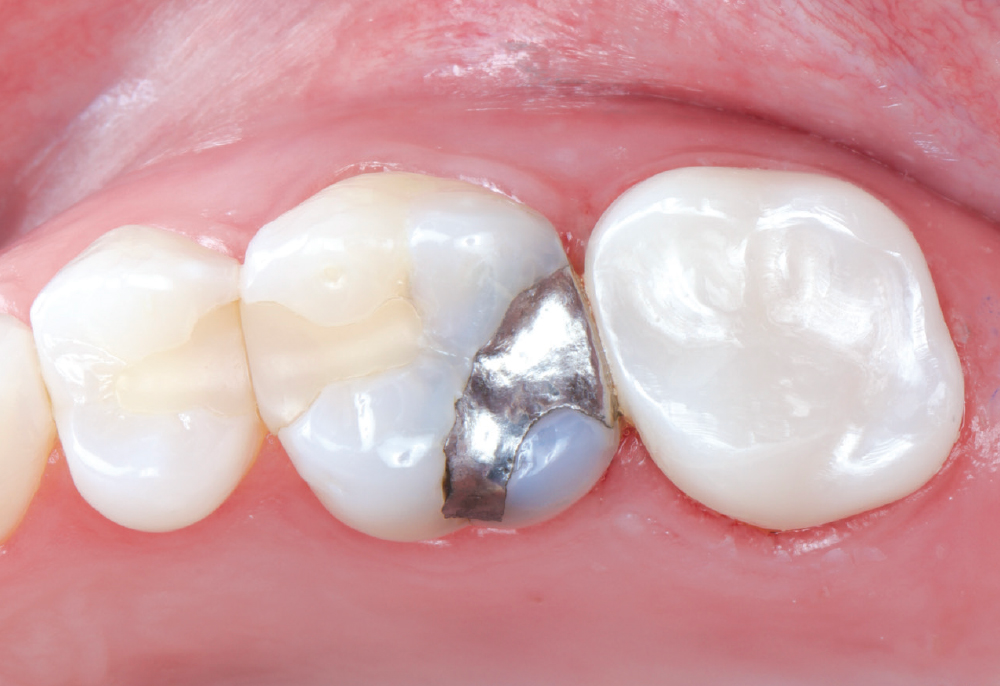

Even though she is a dental hygienist, Nikole decided to wait it out when she was told her crown on tooth #15 had an open margin. But over time, she noticed the area started to shred her floss. That’s when she decided it was time for the crown to be replaced.

Because the patient had high expectations for her restoration, I selected a BruxZir® Esthetic NOW Posterior Milling Block for its combination of esthetics and strength. Though BruxZir Esthetic was originally developed with the anterior in mind, with a yttria content that enhances the overall translucency and color, the material still maintains an excellent flexural strength of 870 MPa, meaning it is sufficiently strong enough to be used anywhere in the arch.